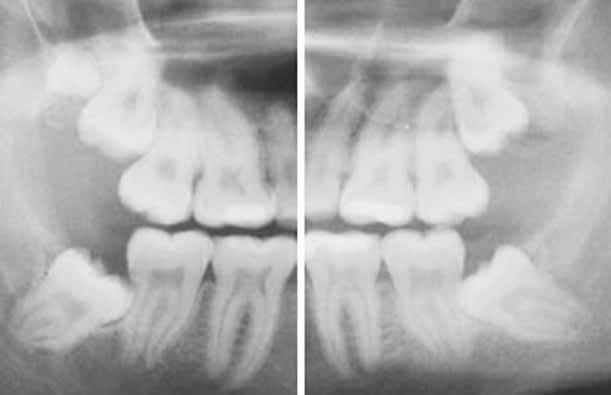

Pour les cas à partager , absolument les deux des patients de mercredi derniers avaient leur prémos extraites, c’est d’ailleurs ce qui a déclenché ce post. est la troisième dont j’ai posté le cliché a une orientation correcte des germes des DDS avec une plage muqueuse importante derrière les 7

Il serait intéressant de noter les indications d’extractions des DDS. si le nivellement rend par le recul des 7 l’éruption de ces dents impossible, il me semble alors que cela doit être dit dés le départ et que les DDS doivent être extraite dès que possible à l’état de germe comme le préconise les recommandations de la HAS. pourquoi attendre la fin du traitement et la phase de contention? ils arrivent à dire qu’une dent posera dans l’avenir des problèmes mais sont incapables de prévoir l’interférence de leur traitement sur l’évolution de cette dent? je ne parle que pour les cabinets que je connais bien et pour encore une fois en avoir discuté avec les orthos dont des amis très proches, ils ne se posent pas cette question et la majorité des cas leurs indications sont à titre prophylactique d’où ce coté systématique qui me dérange, à croire que le seul ,nom de dent de sagesse est une indication d’extraction comme dent mobile serait synonyme d’extraction et implant. Au risque de me répéter , il y a des indications pour intervenir, d’autres pour s’abstenir, le systématique est source de problème pour les patients mais aussi pour les praticiens.Bon week end

Un petit up pour confirmer que sur mes 500 derniers patients adressés ortho en vue DDS, aucun n'a eu les prémolaires d'extraites. Donc tous les orthodontistes n'adressent pas leurs patients pour avulsions préventives des DDS, la plupart posent l'indication...

En pièce jointe un patient qui n'a pas voulu écouter les consignes en 2014 et qui vient finalement de se faire opérer cette semaine.